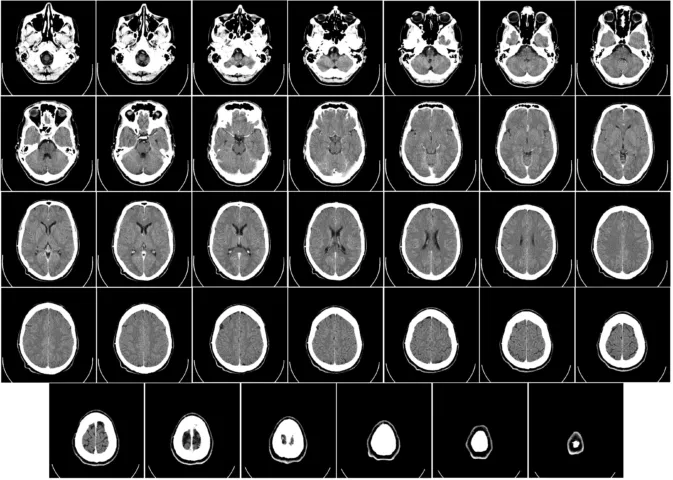

Компьютерная томография мозга человека